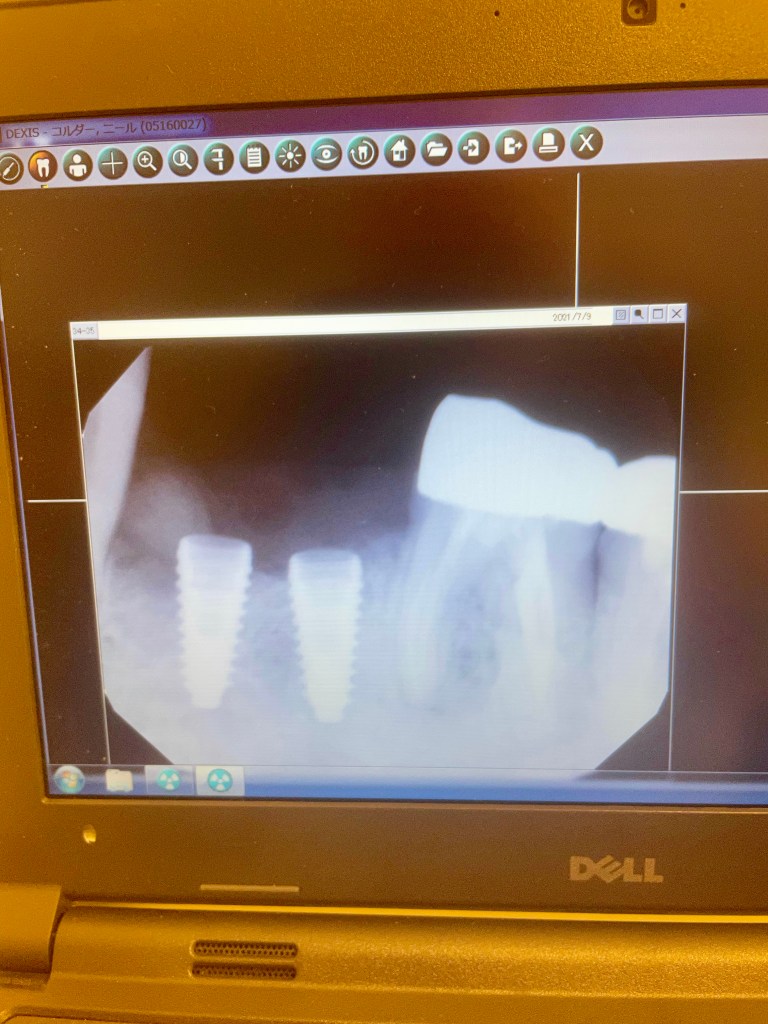

As you know, my teeth are dropping out at a truly alarming rate. What to do to retain any self esteem? Dentures are old-making, bridge apparently not mechanically appropriate in my case. This leaves implants.

An implant is a titanium bolt that is screwed into your jaw bone onto which a crown can be anchored. My friend and long time dentist, Mori Sensei, https://thequietripple.com/2021/03/02/another-one-bites-the-dust/ seems reluctant to do implants. I am do not want to get more dentures. What do dentures do for your sex appeal?

Arisa san points me towards Kinjo sensei’s clinic. It is a very swish place and English speaking. After initial consultation we determine on two implants. Today we do it.

This a proper operation with surgical masks and robes. Kinjo sensei first slices through my gum, which he retracts to either side of the jaw bone. He then does all sorts of stuff until finally drilling deep holes into the jaw. I did not know what was going on at the time but he explained it to me later.